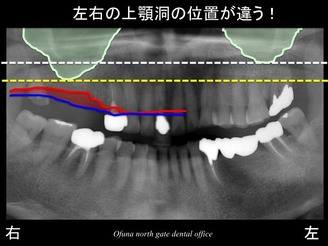

反対側の左側の上顎洞を見てみましょう!

左右の上顎洞の位置を比べると右側の方が下方に下がっているのです。

右側の上顎洞と左側の上顎洞では、その位置が違うのが分かるかと思います。

歯が欠存したために右側の上顎洞が下がってきたのです。

このように比較すると分かりやすいかと思います。